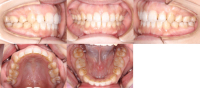

Before

After

- 過蓋咬合前歯のガタガタ

- 治療期間:2年

| 年齢 | 範囲 | 抜歯有無 | 費用 |

|---|---|---|---|

| 23歳3ヶ月 | 全体矯正 | 非抜歯 | 80万円 |